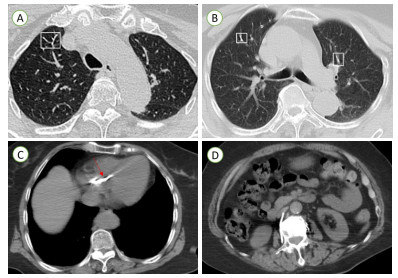

1 病例资料患者,女,71岁,因“检查发现右室异物2 d”入院。患者1个月余前因骨质疏松伴腰2椎体病理性骨折,行经皮椎体成形术。近日拟再次行骨科手术,术前检查发现右心腔内强回声。为进一步手术治疗入院。查体:心率118次/min,血压141/100 mmHg(1 mmHg=0.133 kPa),心前区无隆起,心界向两侧扩大,心律齐,瓣膜听诊区未闻及明显杂音,余正常。辅助检查:心电图检查示:正常心电图。经胸超声心动图检查示:右房室腔内可见一长条状高回声,可见段长约75 mm×5 mm(图 1A~B),不活动,三尖瓣形态、回声及开放活动未见明显异常,右房侧可见少许反流束(图 1C),测三尖瓣口收缩期最大反流速度为2.59 m/s,估测无肺动脉高压(图 1D)。超声诊断:右心腔异常回声,结合临床考虑骨水泥;三尖瓣轻度反流。CT平扫检查示:两肺见条片状致密影,沿血管分支分布(图 2A~B)。心脏形态及大小未见明显异常,右心见条状致密影(图 2C);主动脉钙化;椎体术后改变(图 2D),提示:主动脉钙化。两肺致密影,疑似骨水泥肺栓塞,椎体术后。结合病史,初步诊断:心脏异物、心功能Ⅱ级、腰椎椎体成形术后、骨质疏松。

| 注:A和B为两肺条片状致密影,沿血管分支分布(方框所示);C为右心条状致密影(红色箭头处);D为椎体术后改变 图 2 患者胸腹部CT平扫图像 |